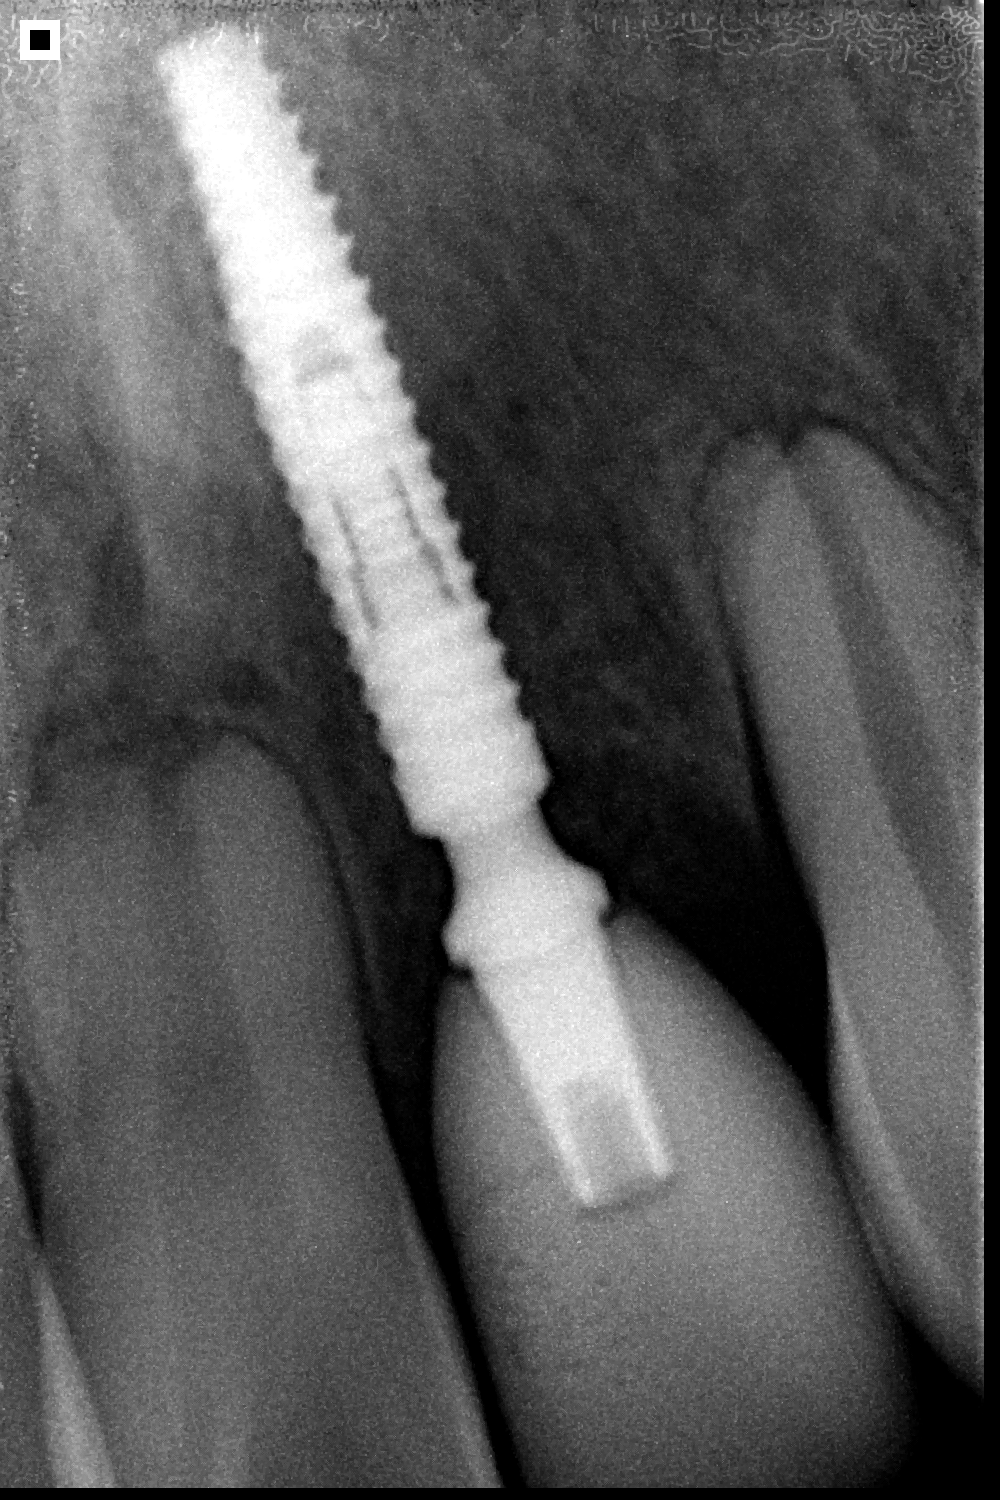

UNITITE SLIM

Con apenas 2.9 mm de diámetro, Unitite Slim proporciona rehabilitaciones en áreas estrechas y espacios interdentales limitados, como las regiones de los incisivos laterales superiores y de los incisivos inferiores.

Ofrece tres longitudes diferentes para su planificación quirúrgica. Su dimensión reducida protege estructuras bucales y su vascularización

Sistema Cono Morse: Superioridad biomecánica de los acoplamientos protésicos con ángulo interno de 3 grados.

Fabricado en titanio grado 4 Cold Worked

Esta técnica de fabricación ofrece estabilidad y resistencia mecánica a longo plazo para

implantes con paredes delgadas.

DIAMETROS UNITITE SLIM

2.9mm

LONGITUDES UNITITE SLIM

10.0mm, 11.5mm, 13.0mm